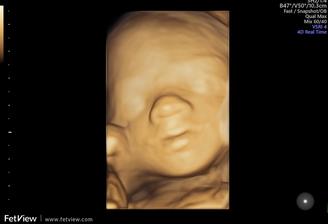

Nase tretie kuriatko😘😙💜